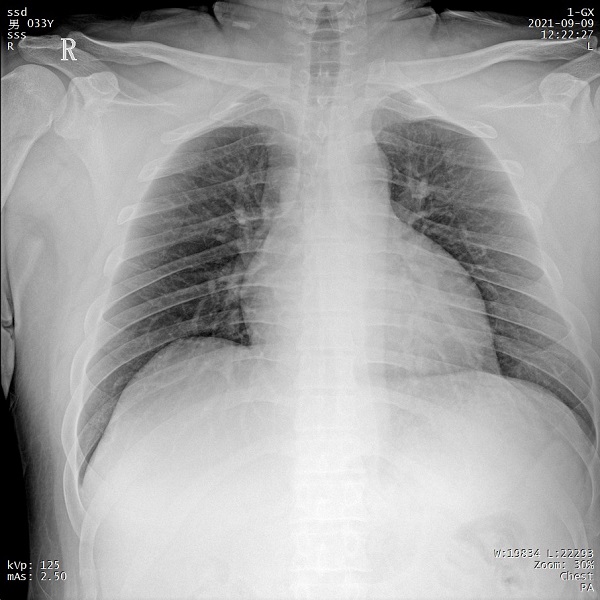

三、支持高千伏攝影 肺部紋理更有層次

PLX5500的最大可調千伏達到150kV,在達到一定高電壓后,與骨骼相重疊的軟組織或骨骼本身的細小結構及含氣的管腔等,均可清晰顯示。